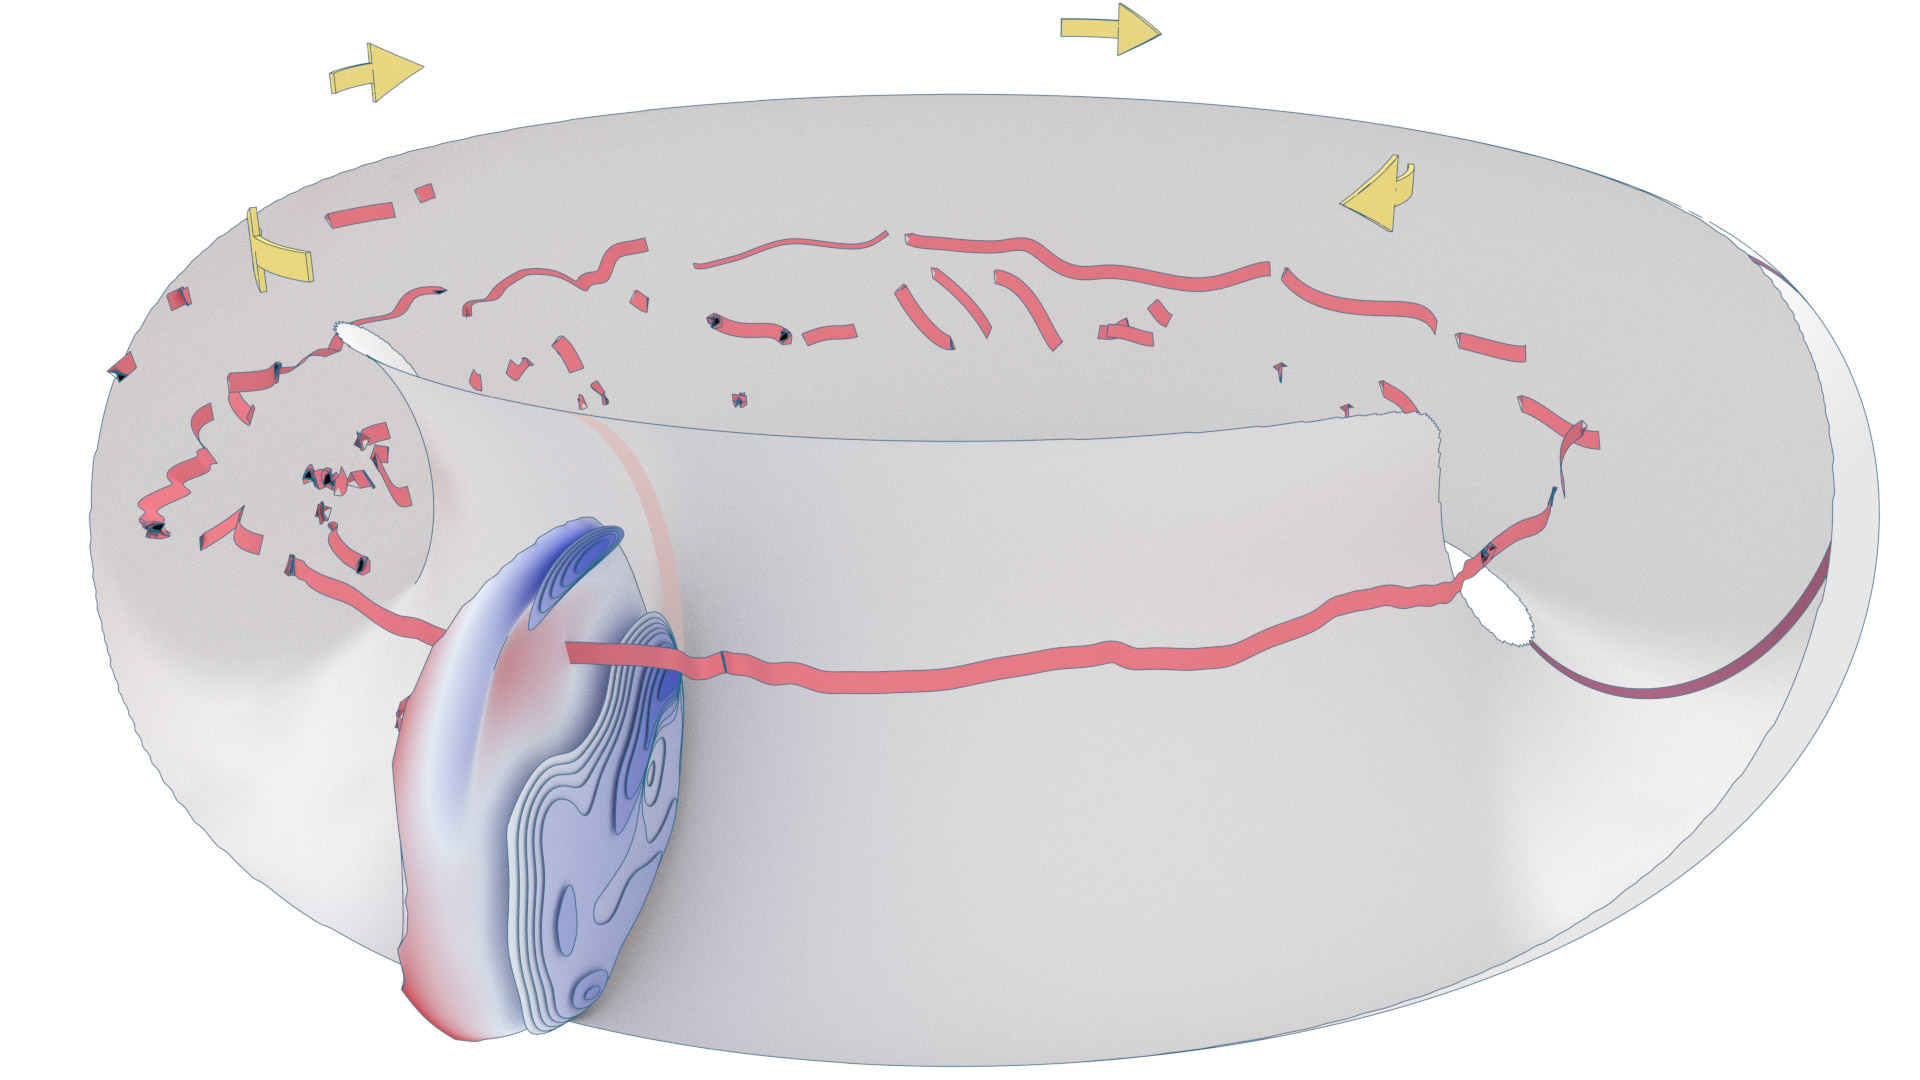

An ongoing collaboration with the Biomedical Simulation Lab (BSL), University of Toronto. In my role, I develop concept sketches and renderings that are then implemented algorithmically. The overall approach is to show turbulent flow visualizations without animation my mapping the transitions among states to carousel that corresponds to the cardiac cycle.